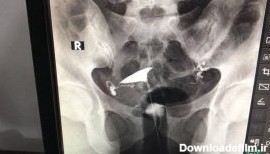

هیستروسالپنگوگرافی؛هیستروسالپنگوگرافی (HSG) نیز نامیده می شود، که یک معاینه اشعه ایکس از رحم و لوله ها است.که در مطب رادیولوژی توسط رادیولوژیست انجام می شود.

عکس رنگی رحم بدون درد؛ هیستروسالپنگوگرافی برای مشاهده داخل رحم و لوله های فالوپ استفاده می شود. می تواند نشان دهد که داخل رحم اندازه و شکل طبیعی دارد یا خیر.

عکس رنگی رحم یا هیستروسالپنگوگرافی یکی از روش های تشخیصی شیوه ی تصویربرداری با اشعه ایکس است که معمولاً برای بررسی آناتومی رحم و لوله ها انجام میشود. عکس رحم

ازمشکلات رحم می توان به ناهنجاری ساختاری رحم که شامل بسته بودن لوله ها یا شکل ظاهری رحم اشاره کردبهترین روش بررسی مشکلات می توان از عکسبرداری رنگی رحم است